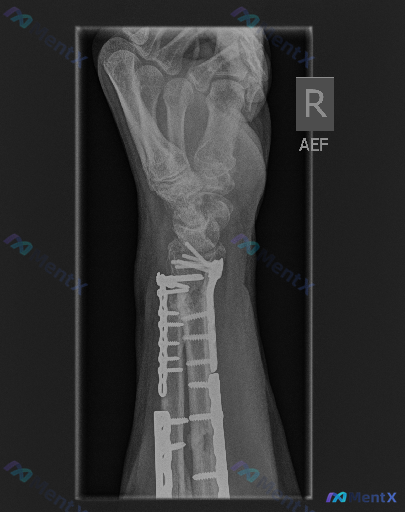

先给大家看一张右手前臂的侧位X光片,是一位外伤术后患者的复查影像。 影像可见:桡骨和尺骨远端均有内固定钢板和螺钉存在,其中桡骨远端为掌侧支撑钢板;钢板固定区域骨折线模糊,骨密度连续性较好,骨痂生长形态良好;钢板和螺钉位置固定牢靠,未见明显断裂或松动;桡骨远端关节面与腕骨对应关系基本正常,腕关节间隙未...